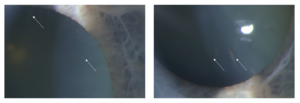

Long anterior zonules (LAZ) is a condition where the zonular fibers extend more centrally on the anterior lens capsule than usual. LAZ is characterized by the presence of zonular fibers that extend more than 1.5-2mm anterior to the equator, and is thought to be remnants of the tunica vasculosa lentis. In some cases of LAZ, persistent pupillary membranes can also be present.

LAZ has been associated with shallowing of the anterior chamber and a thicker crystalline lens with higher risk of angle closure and angle closure glaucoma. Patients with LAZ may also develop K-spindles and heavily pigmented trabecular meshwork, leading to increased intraocular pressure. One variety of LAZ has been linked to age over 50 years, female sex, hyperopia, shorter axial length, and persistent pupillary membrane iris strands. A genetic association has also been identified in some patients with LAZ who have a serine to arginine substitution in the C1QTNF5 gene, causing late-onset retinal degeneration. During cataract surgery, patients with LAZ may be at an increased risk of capsular tears, particularly if there is zonular cutting during the capsulorhexis procedure.